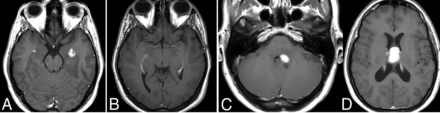

Sentinel inflammatory lesions preceding primary DLBCL of the CNS. Two enhancing periventricular temporal lesions were detected in a patient (A). A biopsy was obtained, and histopathology showed an inflammatory infiltrate without evidence of neoplasia. The lesions disappeared on further imaging controls during the following 2 years (B). In a subsequent MR imaging control, new masslike lesions reappeared (C and D). A biopsy of the new lesions yielded the final histopathologic diagnosis of primary DLBCL of the CNS.

As an additional comment on primary DLBCL of the CNS, it has been reported that “sentinel” inflammatory lesions, which may disappear after anti-inflammatory treatment, can precede the diagnosis of lymphoma by up to 2 years,21 so attention must be paid to the patient’s history of prior inflammatory brain lesions (Fig 3).

Morphologic imaging of this lymphoma is quite characteristic, and the opposite of that of the “typical” CNS lymphoma. It can be deep or hemispheric, with a slightly greater tendency to multiplicity. It is almost constantly highly necrotic with ring enhancement and intermediate-to-prominent signs of hemorrhage. T2WI and DWI signal patterns are both variable and inconsistent. In summary, it is a tumor that differs from the typical appearance of lymphoma and, rather, presents more like the main differential diagnoses, which are glioblastoma and metastasis.8,29,30 A characteristic T2WI heterogeneous hypointensity of the nonenhancing “necrosis,” not corresponding to blood products or mineralization, has recently been suggested in these tumors, in contrast to the usual hyperintense T2 signal of nonhemorrhagic necrosis in other tumors (Fig 4).8

Primary DLBCLs of the CNS, EBV-positive (immunodeficiency/dysregulation-associated). Single (A) and multiple (B) lesions with prominent necrosis (C and E) and tumoral hemorrhage (D and F). Heterogeneous deep T2 hypointensity (H) of the nonenhancing central content (G) of lesions, so-called necrosis. Low-intermediate CBV on the corrected color map (I) and DSC-PWI time-intensity curve with high PSR (J), also very characteristic of this lymphoma subtype.

While conventional imaging is often insufficient to reach a presurgical diagnosis of this challenging entity, quantitative imaging, especially DSC-PWI, can provide diagnostic clues. Indeed, the perfusion features of this lymphoma follow those of low-to-intermediate CBV, high PSR, and the characteristic time-intensity curve morphology when depicting an ROI in the solid parts of tumors (Fig 4).8 Finally, the 1H-MR spectroscopy pattern seems of low value for presurgical characterization as lymphoma because this tumor has prominent mobile lipids overlapping with necrotic glioblastomas or metastasis.20

In conclusion, we suggest that in dealing with a necrohemorrhagic tumor, potential immunodeficiency/dysregulation of the patient must be thoroughly examined. If this cannot be ruled out, DLBCL EBV-positive should be considered, and careful DSC-PWI assessment can provide a presurgical diagnostic clue.